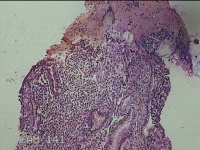

宫腔组织

性别

女

年龄

42岁

临床诊断

异常子宫出血

一般病史

阴道不规则流血49天。

标本名称

大体所见

灰白暗红色不规则碎组织2.5x2x0.8cm一堆。

增生期样反应子宫内膜伴灶性息肉形成。